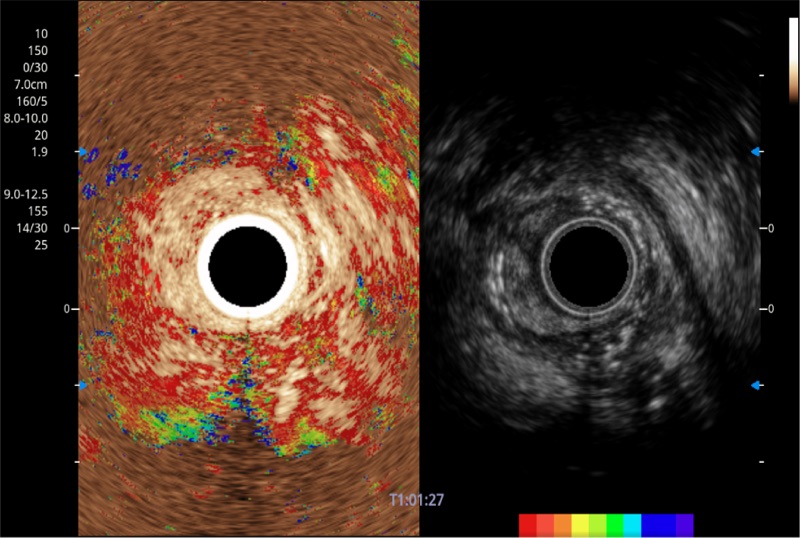

可人为将灰阶图像转变成彩色的显示方式,增强人眼对于不同回声强度的敏感度,主观上增加了图像分辨率

微米成像技术提升了对组织斑点噪声信号的抑制能力,并进一步强化边界信息,从而获得信噪比更优、边界更清楚锐利的图像

食管内间质瘤清晰显像

清晰显示胆总管及周围血管分布